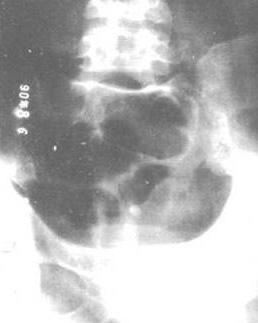

骨神经鞘瘤[1]系骨内神经鞘细胞所产生的良性肿瘤,很少见。好发于下颌骨、骶椎,尺骨干及肱骨干等处,多为20~50岁的青中年男性,肿瘤发展缓慢,病程较长。